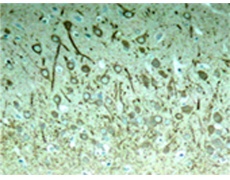

IHC positive control: |

Rat hippocampal region |